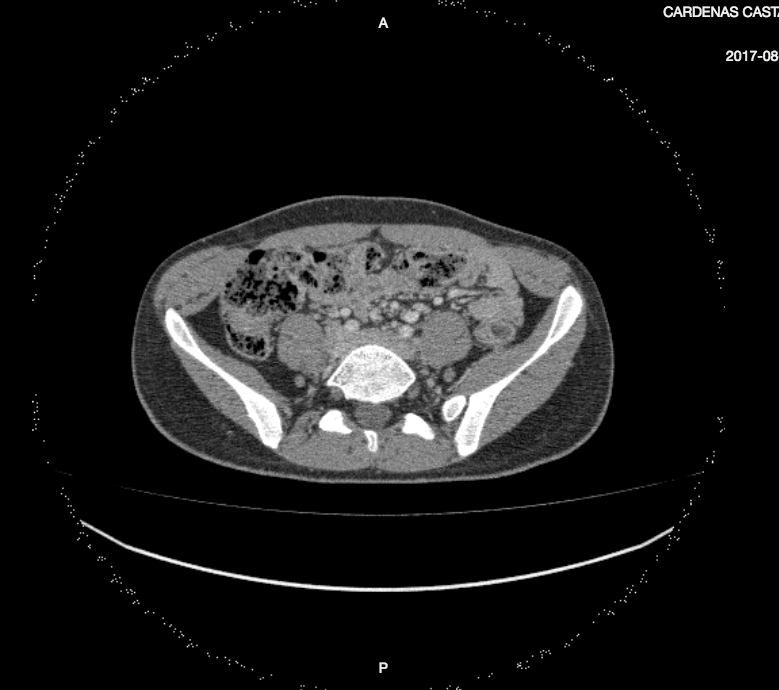

This is how the image is displaying:

And this is how it should be displayed: